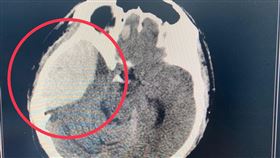

蔡炳坤中風3個月狀況曝!返台中住家休養

台北市副市長蔡炳坤7月餐敘時,因右側大腦出血性中風突...

獨/蔡炳坤何時醒?專家坦言最糟情形

台北市副市長蔡炳坤7月11日晚間餐敘時,因右側大腦出...

蔡炳坤「1個月未醒」康復「2關鍵」

台北市副市長蔡炳坤,上月11日與市長柯文哲出席餐敘時...

蔡炳坤腦中風仍昏迷 最新病況曝光

蔡炳坤「腦中線偏移」醫曝因腫脹太大

蔡炳坤最新病況!聯醫:腦壓正常

台北市副市長蔡炳坤,11日晚間在用餐時突然昏倒,開刀...

北市副市長蔡炳坤用餐到一半緊急送醫,診斷後發現是「右...

蔡炳坤腦中風 重症醫曝1舉動救人

台北市副市長蔡炳坤,昨(11)日晚間在用餐時突然昏倒...

蔡炳坤腦出血!醫驚曝「1誘發原因」

台北市副市長蔡炳坤昨(11)日晚間用餐時昏迷,緊急送...